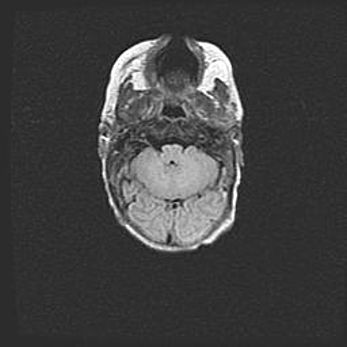

Подострая гематома правой гемисферы мозжечка.

Наружная гидроцефалия.

Возраст: 15 дней

Вес: 3100 г

Пол: женский

Окружность головы: 37 см

Срок гестации: 35-36 недель

При открытой наружной форме гидроцефалии у новорожденных расширяются и переполняются субарахноидные пространства.

Кровоизлияния в мозжечок имеют две клинико-анатомические формы: полушарные гематомы и кровоизлияния в червь.

К появлению этой патологии может привести: повреждения головного мозга, возникающие в результате асфиксии и гипоксии плода при беременности, или травмы во время родов. Редко гематома мозжечка может быть результатом первичной коагулопатии и сосудистой мальформации, диссеминированном внутрисосудистом свертывании, изоиммунной тромбоцитопении.